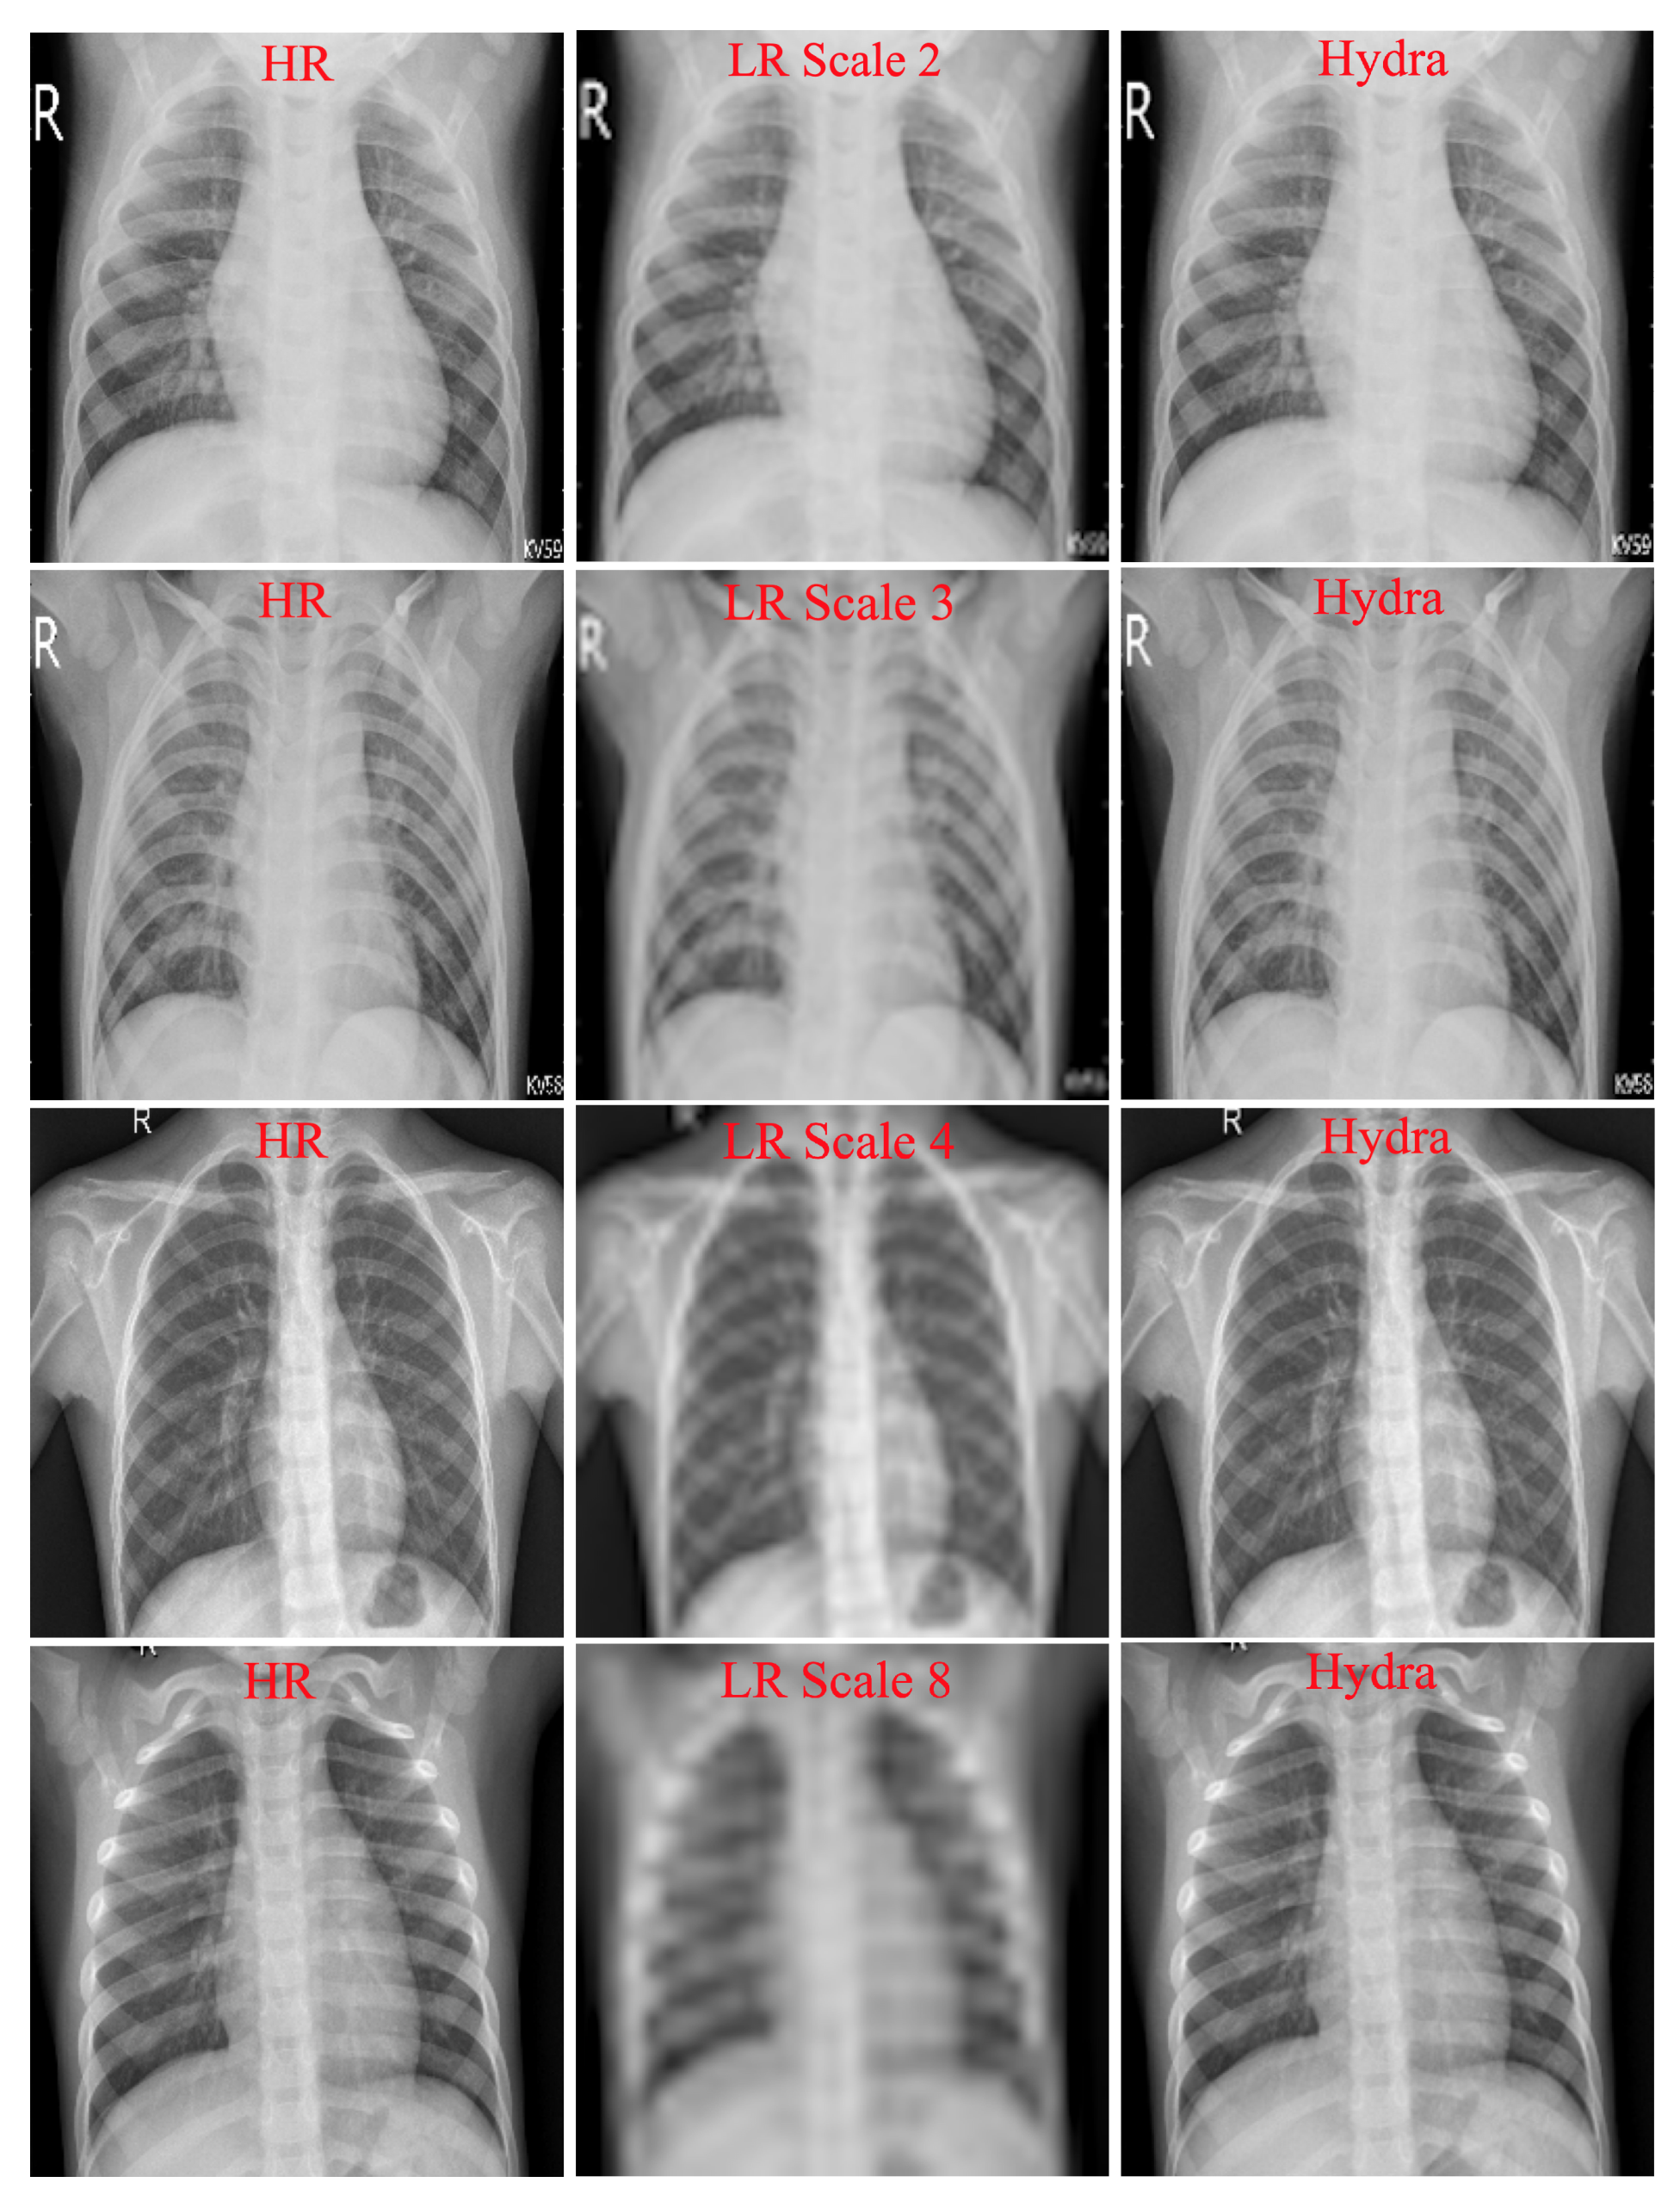

4.1. Hydra Trunk Performance

- Multiple Scales Training: Our SISR model is trained with different scale factors at once. The trained network can then be tested with any scale used during training. As discussed in [21], training a single model with multiple scale factors is more efficient, accurate, and practical as compared to training and storing several scale-dependent models.

- Context: We utilize information from the entire image region. Existing methods either rely on the context of small image regions (e.g., [20]) or large image regions (e.g., [21]), but not the entire image region. Our experimental results demonstrate that using the entire image region leads to better overall performance while decreasing computations.

- Raw Image Channels: We propose to compute the residual image from the raw image (RGB or grayscale) directly instead of converting the images to a different color space (e.g., YCbCr [21]). The residual image is computed by subtracting the HR reference image from the LR image that has been upscaled using interpolation to match the size of the reference image. The computed residual image contains information of the image’s high-frequency details. The main benefit of directly working on the raw color space is that we decrease the total computational time by dropping two operations: (1) converting from raw color space to another color space (e.g., YCbCr) and (2) converting the image back to its original color space. Our customized SISR model computes the residual images directly from the original color space and learns to estimate these images. To construct an HR image, the estimated residual image is added to the upsampled LR image.